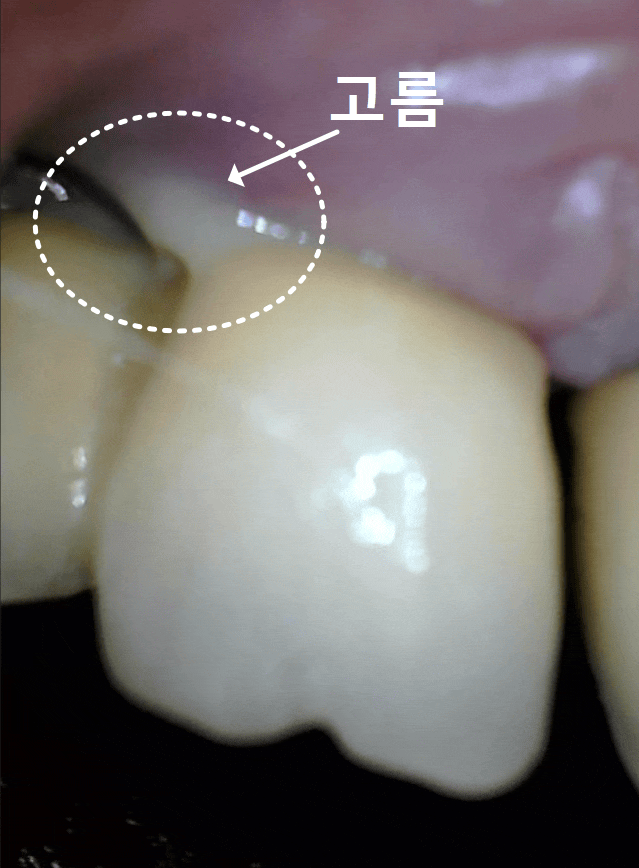

불편함을 호소하시는 환자분의 입안을 보니,

상황은 생각보다 좋지 않았는데요..

잇몸은 붉게 부어올라 있었고,

살짝만 눌러도 노란 고름이 배어 나오는 상태...

230216